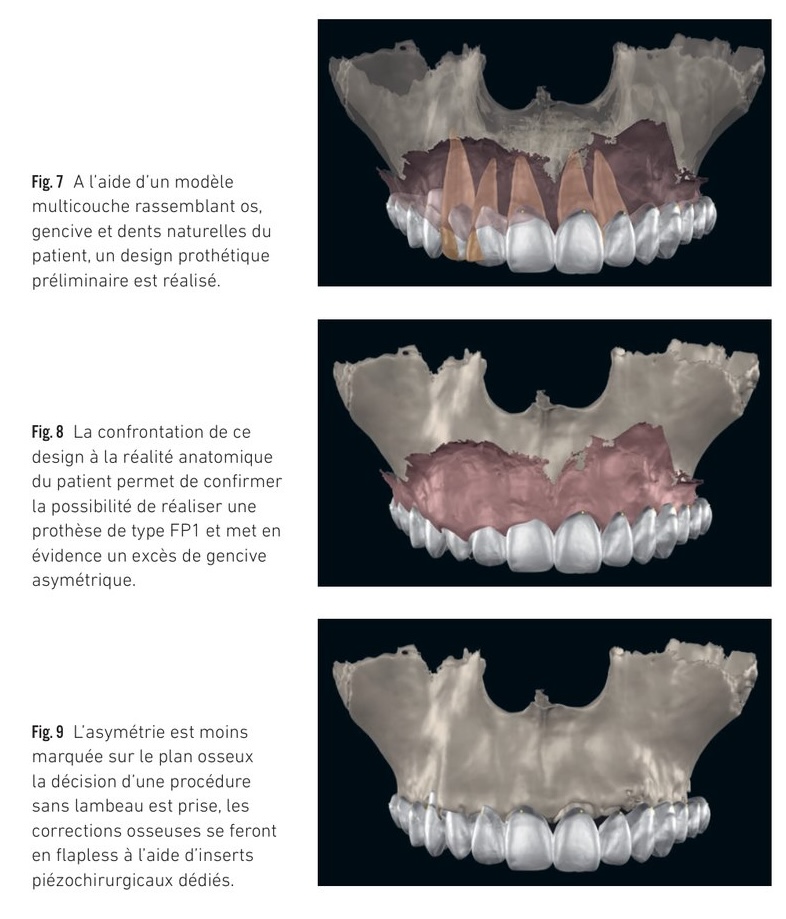

Ce deuxième temps est essentiel car il va permettre de confronter le résultat esthétique idéal au volume osseux du patient dans un rapport intermaxillaire correct et d'en déduire la restauration prothétique la plus adaptée à la situation clinique du patient.

En fonction de l'espace disponible entre le rebord osseux et le bord libre des futures dents prothétiques, trois types de reconstructions seront indiqués selon la classification de Misch :

• dans le cas d'une résorption faible, reconstruction de type FP1 : prothèse conjointe conventionnelle sans fausse gencive. Dans cette indication, la plus grande précision est nécessaire aux émergences implantaires, qui doivent toutes être strictement dentaires en évitant les espaces interproximaux, sous peine de compromettre fortement le résultat esthétique final.

• dans le cas d'une résorption moyenne, reconstruction de type FP2 : la prothèse peut présenter des émergences radiculaires ou un tout petit peu de fausse gencive, mais se rapproche aussi d'une prothèse conjointe conventionnelle. Cette classe est intermédiaire, il s'agit de la catégorie de patients la plus fréquente aujourd'hui et elle combine les exigences des restaurations de type FP1 et FP3.

• dans le cas d'une résorption importante, reconstruction de type FP3 : la prothèse comporte une portion importante de fausse gencive. Dans cette indication, le positionnement implantaire nécessite également une moindre précision puisque l'émergence de ces derniers doit se faire dans le couloir prothétique. Il est important dans ces indications de retrouver des plans osseux et muqueux horizontaux strictement parallèles aux lignes de référence de la face pour éviter toute rétention alimentaire au niveau de l'extrados prothétique.